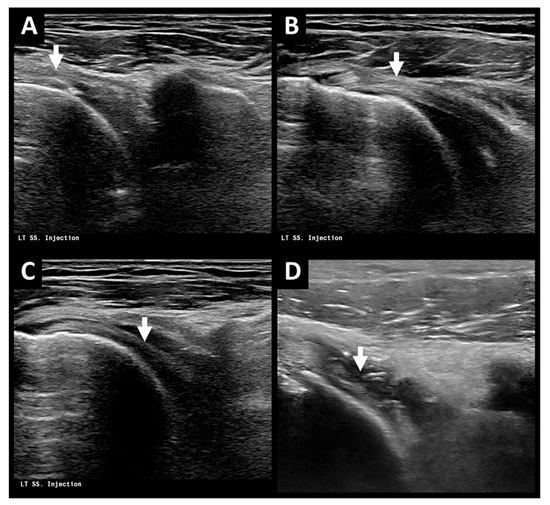

From www.nysora.com

Case Study Adhesive Capsulitis Injection NYSORA NYSORA Adhesive Capsulitis Ultrasound Parameters Specific signs of adhesive capsulitis on ultrasound evaluation include thickening of the inferior recess of the glenohumeral joint. Axillary pouch thickening, reduced sliding of the infraspinatus tendon, and thickening of the shoulder pulleys are typical ultrasound. Heat therapy modalities, which aim at modifying dense collagenous tissues are commonly practiced interventions for patients. Adhesive capsulitis (ac) of the shoulder, also referred. Adhesive Capsulitis Ultrasound Parameters.